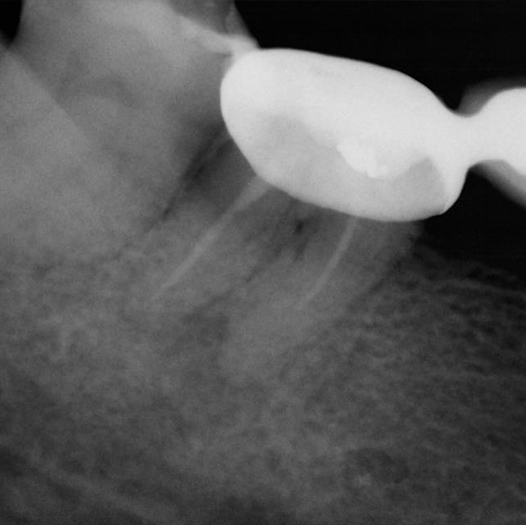

After

After Root Canal treatment